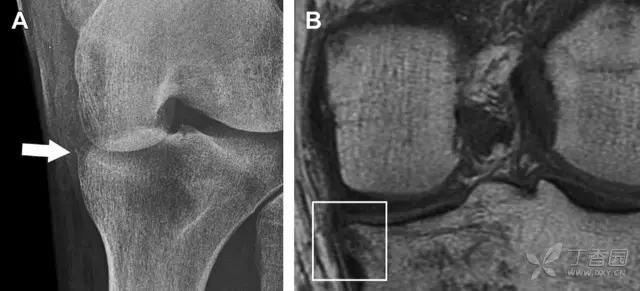

一位足球运动员的 Segond 骨折。A 正位片示关节线下方胫骨外侧皮质撕脱(箭头)。B MRI 冠状位 T1 加权像示附着于髂胫带的骨折碎片(空箭头)(来源:Radiol Clin N Am 53 (2015) 737–755,YU,Ohio)

一位足球运动员的反向 Segond 骨折。A 正位片示关节线处的胫骨内侧见一细小骨折片(箭头)。B MRI 冠状位 T1 加权像示骨折片出现在内侧副韧带关节囊附着处(方框)(来源:Radiol Clin N Am 53 (2015) 737–755,YU,Ohio)